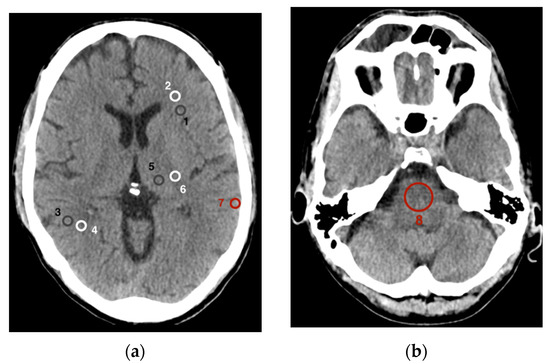

2.3. Quantitative Image Analysis